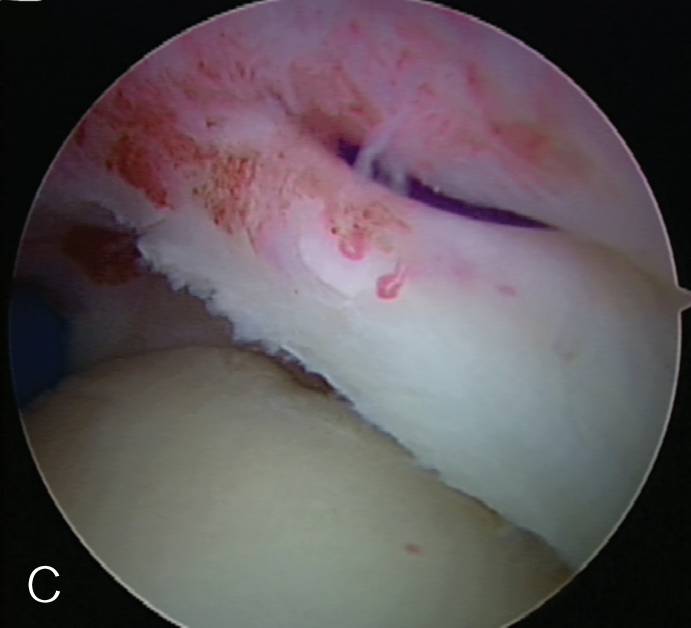

修复处准备